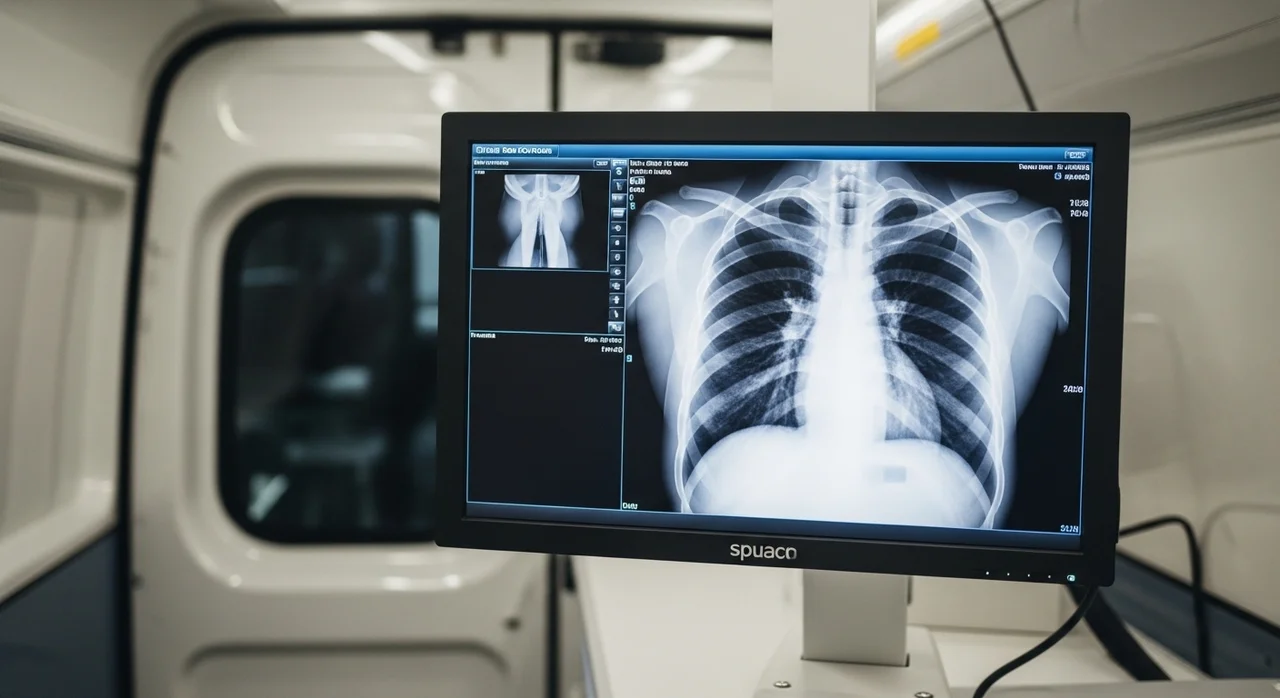

대한결핵협회와 보건소가 협력하여 검진 차량이 직접 학교로 방문합니다. 별도의 비용 없이 흉부 엑스레이 촬영을 통해 빠르고 정확하게 건강 상태를 체크할 수 있는 기회예요.

흉부 X-선 촬영 실시

전문 방사선사의 안내에 따라 안전하게 촬영을 진행하며, 소요 시간은 1인당 1분 내외입니다.